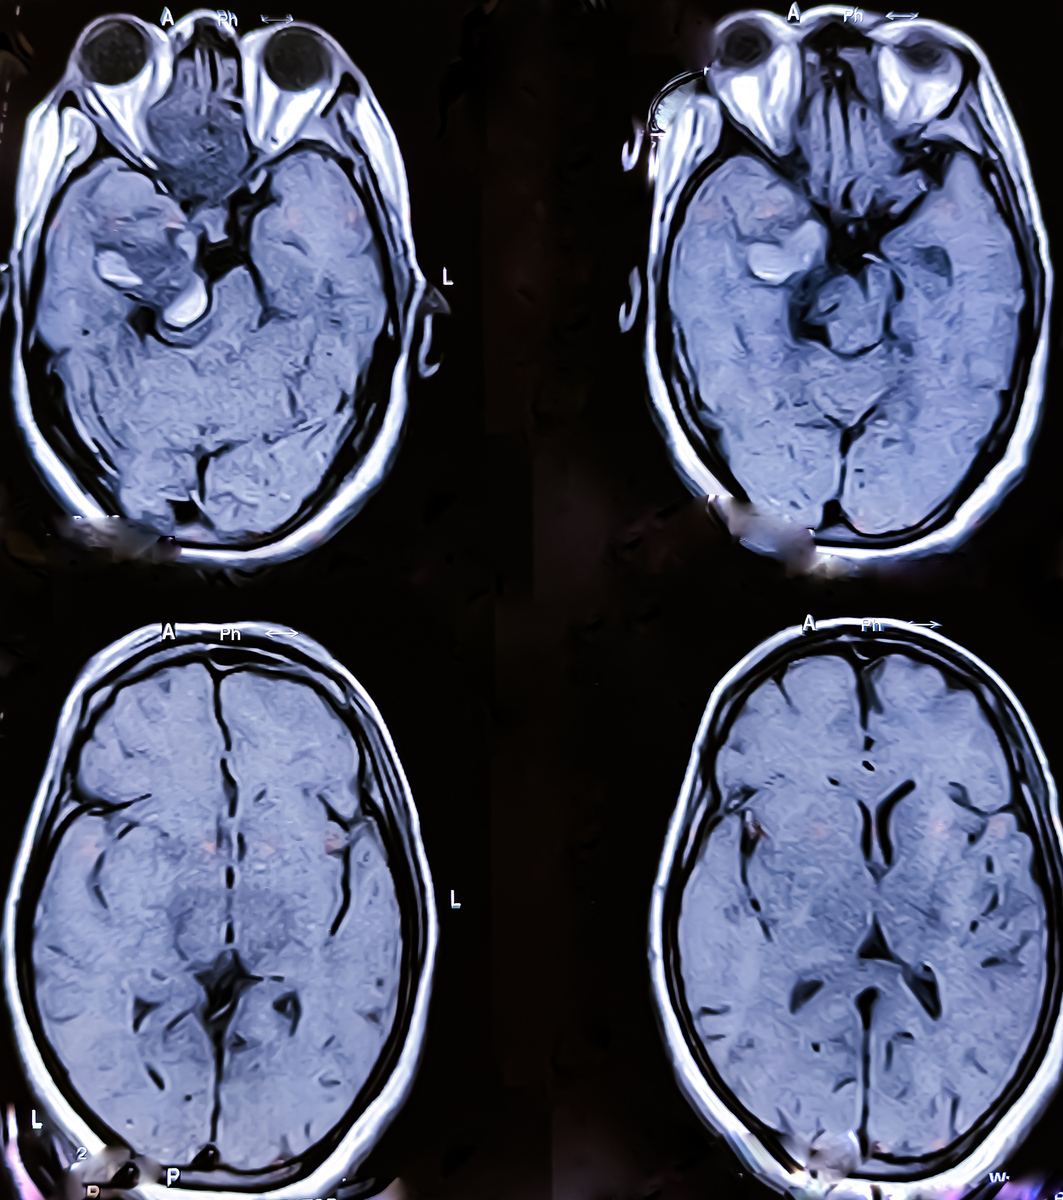

大脑中动脉主干闭塞 '三偏'症状,伴头/眼向患侧凝视,优势半球受累可伴失语症 非优势半球受累可伴体象障碍;可出现意识障碍

大脑中动脉上部分支闭塞 对侧面部、上下肢瘫痪和感觉缺失,但下肢瘫痪较轻,足部不受累,头/眼向患侧凝视程度轻 伴Broca失语(优势半球)/体象障碍(非优势半球),通常不出现意识障碍